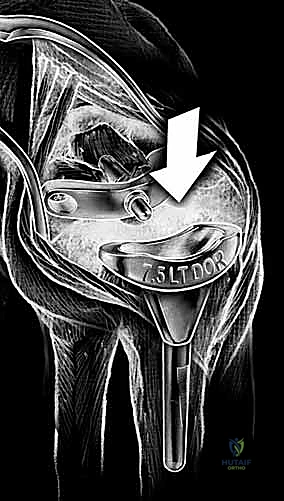

The evolution of modern implant design has capitalized on modularity, superior tribology, and improved anatomic geometries to provide enhanced longevity. A great debt of gratitude is owed to Dr. Jay Menon for popularizing stable distal screw fixation into the carpus, fundamentally altering the biomechanical paradigm by avoiding the destructive lever arm created by a long intramedullary stem inserted into the third metacarpal. Today, the three most popular wrist designs utilized in the United States are the Universal 2 (KMI/Integra), the Re-Motion (Small Bone Innovations [SBI]), and the Maestro (Biomet). The Universal 2 Total Wrist prosthesis, an improved version of Dr. Menon's original design, utilizes a flat carpal cut, screw fixation distally into both the second metacarpal and hamate, and a modular, distally based polyethylene cap that articulates with a proximal cobalt chrome radial component.

Normal anatomic parameters of the distal radial articular surface include a volar tilt of approximately 11 degrees and a radial inclination of 22 degrees. Recreating these spatial relationships is a fundamental goal of modern implant systems. The Re-Motion Total Wrist, for instance, is fundamentally designed to resurface the distal radius while allowing about 15 degrees of intended "wiggle" or toggle built into the snap fit of the polyethylene cap with the carpal plate, compensating for minor kinematic mismatches. Conversely, the Maestro Wrist utilizes a metal convex component articulating with a concave polyethylene component, mimicking successful total hip and shoulder designs, and features a modular titanium stem designed to achieve diaphyseal fill and rotational stability.

With the wrist held in neutral, the radius is scored through the cutting slot in the guide to provide a reference for the distal radial resection. The thumbscrew on the carpal resection guide is loosened to allow insertion of the radial resection guide boom. Following radial resection, the scaphoid, capitate head, hamate edge, and triquetrum are resected at a precise 90-degree angle to the axis of the forearm jig. The trial carpal plate is provisionally determined by the curvature and width of the remaining proximal carpal surface; it must lie flush with the hamate and proximal capitate surfaces. Unlike older designs, it is not always necessary to attempt fusion of the distal pole of the scaphoid to the surrounding carpus. The Maestro Wrist has a provision to replace the entire scaphoid using a carpal plate incorporating a modular radial augment, of which three separate sizes are available.

Following capitate reaming, the chosen carpal plate and stem are assembled and inserted into the capitate and seated onto the resected carpal surface. The carpal plate is anchored to the carpus with a radial screw that optimally does not penetrate the second metacarpal, and a second screw placed ulnarly into the hamate. This construct ensures stable distal fixation while avoiding the deleterious lever arm of a long metacarpal stem. Trial reductions are performed to assess stability, range of motion, and impingement. Once kinematics are confirmed, the definitive ultra-high-molecular-weight polyethylene (UHMWPE) body—which is direct compression molded onto a cobalt chrome alloy radial body—is impacted. The capsule and extensor retinaculum are meticulously repaired to prevent extensor tendon bowstringing and provide a robust soft tissue envelope over the implant.